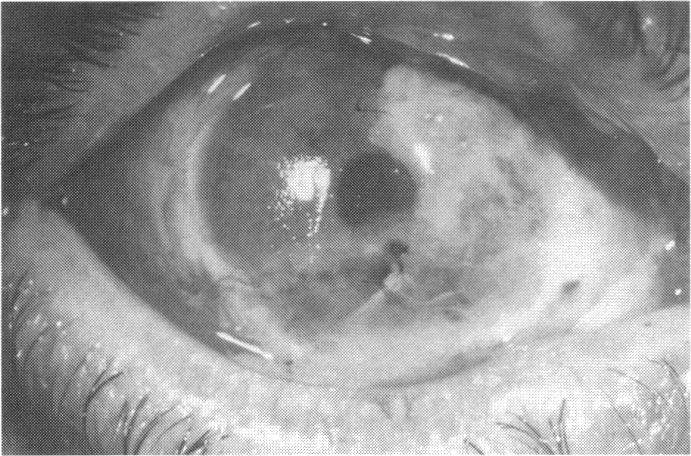

RESULTS

Human subjects. Of the 19 total patients admitted to the study, the presumed corneal epithelial stem cells of 1 patient did not grow in vitro. Of the remaining 18 patients (20 procedures, 19 eyes), 3 patients had unsuccessful results (3 autologous procedures), 1 patient had a partially successful procedure (allogeneic procedure), and 1 patient had a procedure with an undetermined result at present (allogeneic procedure). One unsuccessful patient had entropion/trichiasis and mechanically removed the graft and eventually went into phthisis. The other 2 unsuccessful patients suffered presumed loss of autologous donor epithelium and recurrence of the ocular surface disease (pterygium). The partially successful patient receiving an allogeneic transplant had infectious keratitis delay of his re-epithelialization; he has only minimal visual improvement but has re-epithelialized. The patient receiving the second allogeneic graft lost his donor epithelium at day 4. Additional donor epithelium was reapplied, but the result is undetermined at present. Amniotic membrane as carrier. The in vitro preparation of the amniotic membrane with corneal epithelial stem cell graft overlay was successful. Histology documented removal of the amniotic epithelium and reapplication of corneal epithelial cells. Animal model. The 2 rabbits that had no reparative surgery following standard ocular surface injury had histology and immunopathology consistent with incomplete corneal epithelial stem cell failure with vascularization and scarring of the ocular surface. Light microscopy and immunohistologic staining with AE5 confirmed the conjunctival phenotype of the ocular surface repair but also documented the incomplete model. The allogeneic stern cell transplants had varying results. One rabbit had a suppurative infection and lost the graft. Reparative surgery failed in 2 of the rabbits, failed partially in 3 of the rabbits, was partially successful in 3 others, and was successful in 1 rabbit at 28 days. Histologic and immunopathologic study documented successful growth of corneal epithelium onto the recipient surface.

结果

人类受试者。纳入研究的19例患者中,1例患者的假定角膜上皮干细胞在体外未生长。其余18例患者(20例手术,19只眼)中,3例患者手术结果不佳(3例自体手术),1例患者手术部分成功(异体手术),1例患者目前手术结果未确定(异体手术)。1例手术失败的患者患有睑内翻/倒睫,机械性移除了移植物,最终眼球萎缩。另外2例手术失败的患者假定自体供体上皮丢失且眼表疾病(翼状胬肉)复发。接受异体移植的部分成功患者发生感染性角膜炎,上皮化延迟;他的视力仅略有改善,但已重新上皮化。接受第二次异体移植的患者在第4天失去了供体上皮。重新应用了额外的供体上皮,但目前结果未确定。羊膜作为载体。羊膜与角膜上皮干细胞移植物覆盖物的体外制备成功。组织学证实羊膜上皮已去除且角膜上皮细胞已重新应用。动物模型。2只在标准眼表损伤后未进行修复手术的兔子的组织学和免疫病理学结果与角膜上皮干细胞不完全衰竭一致,伴有眼表血管化和瘢痕形成。光学显微镜检查和用AE5进行的免疫组织化学染色证实了眼表修复的结膜表型,但也记录了不完全模型。异体干细胞移植结果各异。1只兔子发生化脓性感染,移植物丢失。2只兔子的修复手术失败,3只兔子部分失败,另外3只部分成功,1只兔子在28天时成功。组织学和免疫病理学研究记录了角膜上皮在受体表面的成功生长。